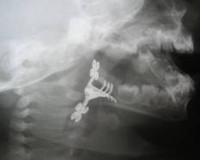

T17.2 Инородное тело в глотке